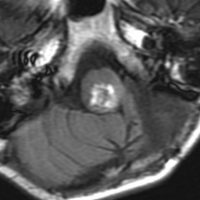

乳児の髄芽腫の治療後の硬膜血管腫

生後8ヶ月で髄芽腫を発症して,手術後に8コースの化学療法して,残存腫瘍があったために2歳半で脳脊髄照射18グレイと後頭窩局所照射21.6グレイをしました。放射線治療後2年で見つかった左前頭部腫瘍です。てっきり脳表播種再発かと思いましたが,良性の硬膜血管腫でした。この子は20歳となり再発もなく元気です。幼児期の放射線治療あるいは化学療法は,予想より早期に,珍しい2次腫瘍を誘発することがあると考えたほうがいいのでしょう。この腫瘍の部位には1日線量1.8グレイで18グレイしか照射されていませんでした。